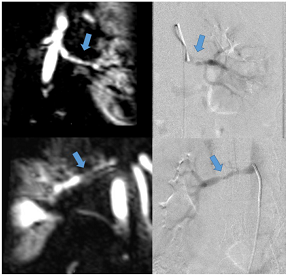

7. CMR Stress Perfusion

Hypertension is a well-established atherosclerotic risk factor for the evolution of coronary artery disease (CAD). Both macrovascular CAD of the epicardial coronary arteries and microvascular CAD (small vessel disease with endothelial dysfunction) are detectable by CMR stress perfusion [36]. There is an increased frequency of hypertension in patients with chest pain, angiographically normal coronary arteries, and microvascular CAD, which may be detected by CMR using visual assessment or perfusion quantification techniques [31].

CMR stress perfusion essentially visualizes myocardial first-pass perfusion during pharmacological stress. Images are interpreted in conjunction with rest perfusion images and late gadolinium enhancement (LGE) images. In the presence of a significant epicardial coronary stenosis, the myocardial contrast uptake is reduced in a specific coronary territory (coronary pattern). Conversely, microvascular dysfunction displays a more diffuse and delayed but synchronous myocardial contrast uptake during stress. Stress CMR offers excellent sensitivity and specificity for the detection of anatomically and functionally significant CAD [37] and allows risk stratification irrespective of LVEF, the presence of CAD, symptoms, and LGE [38]. The assessment of quantitative myocardial blood flow has prognostic value and is likely to be used in the clinical routine in the near future [39].